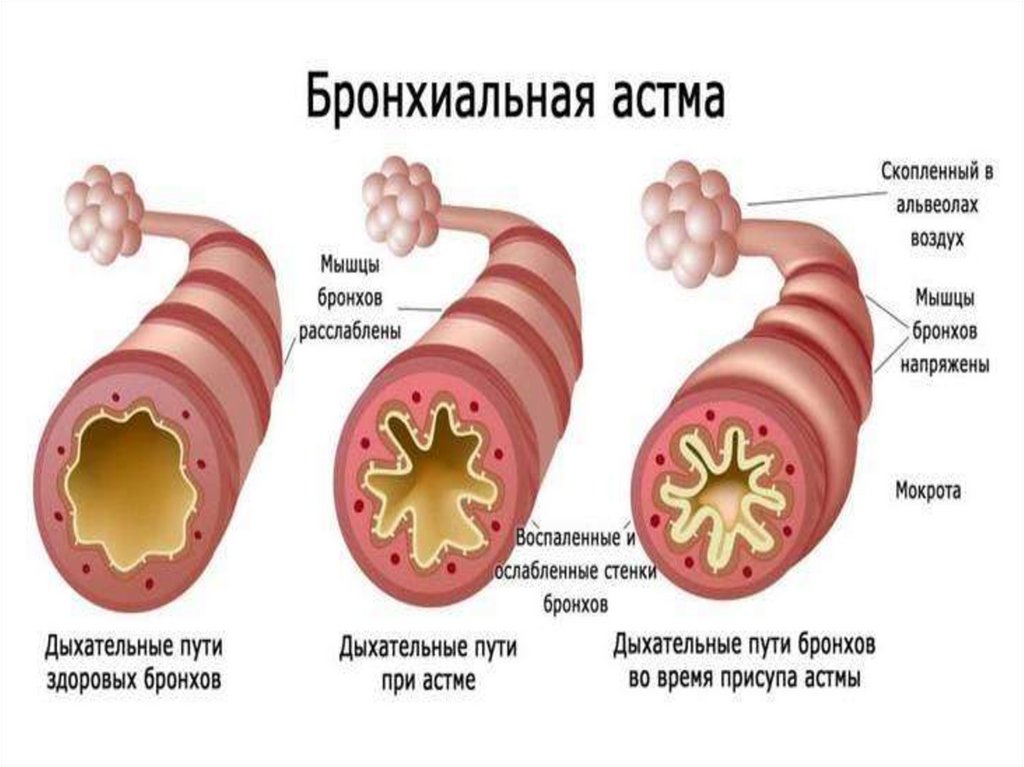

Еда для Легких и Бронхов - Полезные Рецепты